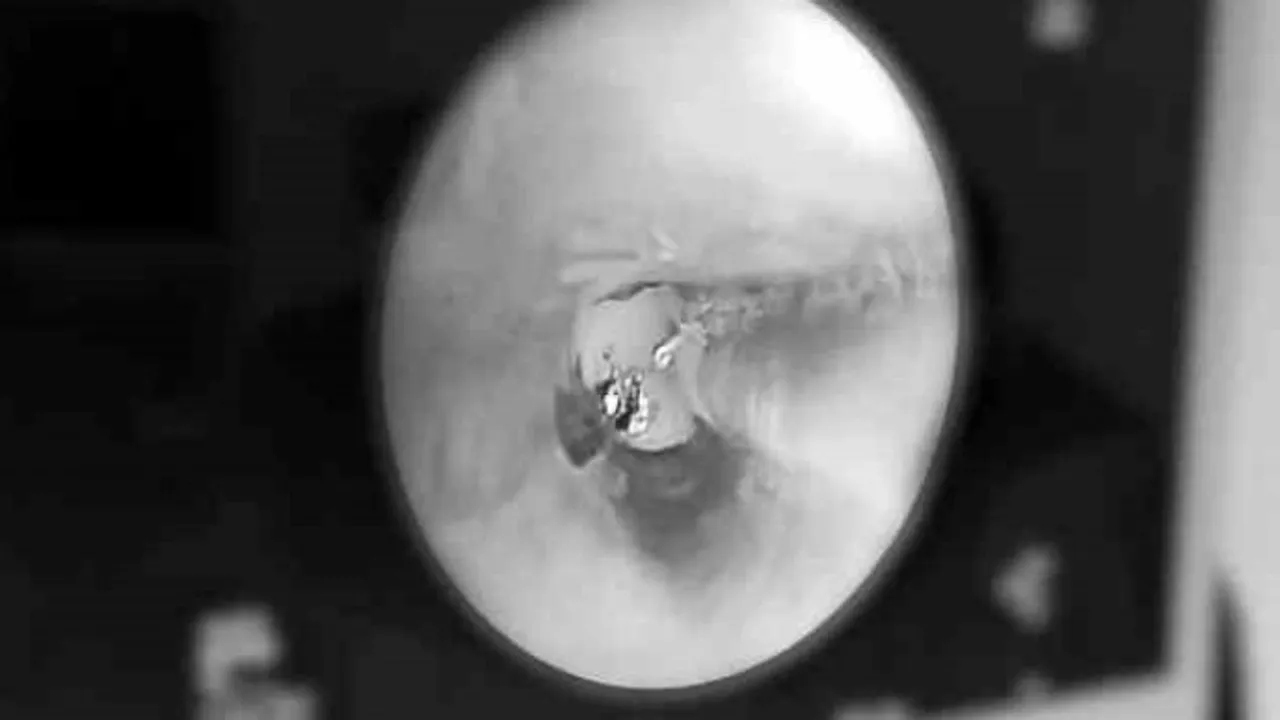

Rezektör balon tedavisinin etkilerinden bahseden Göğüs Cerrahisi Uzmanı Doç. Dr. Hüseyin Ulaş Çınar, “Rezektör balon tedavisi, kronik bronşit nedeniyle oluşmuş KOAH'ta, daralan hava yollarının, üzeri örtülü bir balon yardımıyla genişletilmesi ve beraberinde havayollarında mukus üretimini sağlayan goblet hücrelerinin parçalanarak köpük halinde temizlenmesi işlemidir. Rezektör balon tedavisini genel anestezi altında uyguluyoruz. Yaklaşık 1-2 saat sürüyor. İşlem sonrası 1 gün yoğun bakım ve 1-2 gün takip süresinden sonra hastaları taburcu ediyoruz. Ağır KOAH'ta nefes darlığı nedeniyle yürümekte bile zorlanan hastalar, işlem sonrası günlük yaşamlarına devam edebilecek düzeye geliyorlar. Ancak bu tedavi belli derecenin üzerindeki KOAH hastalarında faydalı olmakta. Hastalığın derecesini fev1 dediğimiz tıbbi terim üzerinden değerlendiriyoruz. Yüzde 80 fev1 değerine sahip hastalar normal kişi olarak değerlendirilebilir. Bu değerin yüzde 50'nin altına düşmesi alarm verici düzeydir. Yüzde 30'un altına düşen hastalar ise bir süre sonra akciğer nakline aday olabilir. Biz yüzde 50'nin altına düşmeyen hastalarda rezektör balon tedavisini düşünmüyoruz. Genel olarak yüzde 30-50 arasında fev1 değeri olan hastalarda uygulanması öneriyoruz” diye konuştu.

Evde yardımcı solunum cihazı olmadan nefes almakta zorlanan hastanın tedavinin hemen sonrasında büyük bir iyileşme kat ettiğini dile getiren Dr. Çınar, “Hastamız 10 yıldır KOAH nedeniyle takip edilen bir hasta. Çeşitli medikal tedavilerle günlük yaşantısını idame ettirmeye çalışıyordu. Oksijen bağımlısı olarak günlük hayatına devam etmek zorundaydı. Son yaptığımız muayenede hastanın fev1 değerinin yüzde 20'nin altına düştüğünü gördük. Akabinde hastanemiz akciğer hastalıkları komitesinin kararı ile rezektör balon tedavisinin yapılmasına karar verdik. Hastamız işlem sonrası 1. günde oksijenden bağımsız bir şekilde günlük aktivitelerini yapacak konuma geldi. İşlem öncesi yüzde 18 olan fev1 değeri, işlem sonrası 12. saate yüzde 44'e kadar yükseldi. Rezektör balon tedavisi gelecekteki KOAH tedavisi açısından umut verici bir tedavi yöntemi. Bu tedavi yönteminin patenti ilk olarak 2006'da bir Türk profesör tarafından alındı. 2010 yılından itibaren de çeşitli kanser hastalıklarının tedavisinde kullanılan bu yöntemin KOAH'ta kullanılmaya başlaması da 2015 yılından itibaren arttı” şeklinde konuştu.